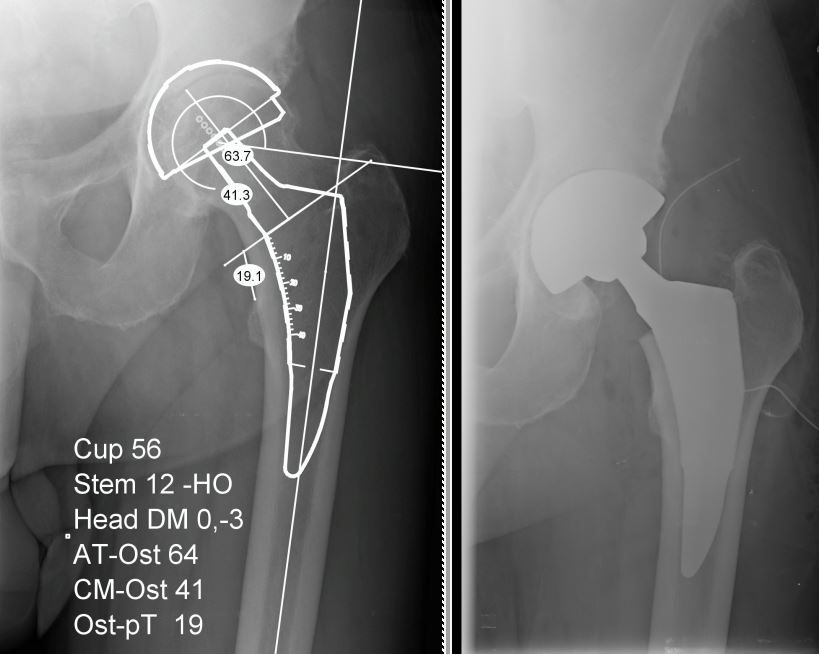

Il Dr. Giuntoli si è laureato in Medicina e Chirurgia nel 2014 presso l’Università degli Studi di Firenze e successivamente nel 2020, ha conseguito la Specializzazione in Ortopedia e Traumatologia presso l’Università degli Studi di Pisa con votazione di 110/110 e Lode, discutendo la tesi: “I sensori di pressione nella Protesi Totale di Ginocchio: confronto clinico e funzionale mediante Gait Analysis tra la tecnica convenzionale e il sistema VERASENSE”. Dal 2021 al 2024 ha svolto attività clinica, chirurgica ed universitaria presso la U.O. Ortopedia e Traumatologia I Universitaria dell'Azienda Ospedaliero Universitaria Pisana (AOUP) nell'Ospedale di Cisanello di Pisa Da gennaio 2023 svolge attività di docenza di ecografia muscoloscheletrica diagnostica e procedurale (infiltrativa) presso la scuola SIUMB di Pisa, di cui è anche docente dal 2024 presso l'Università di Pisa. Attualmente Dirigente Medico presso il CESAT (Centro Eccellenza Sostituzione Articolare Regione Toscana) - Ospedale San Pietro Igneo di Fucecchio, presso la quale svolge la maggior parte dell'attività clinica, chirurgica e di ricerca soprattutto nell'ambito della protesica di anca e ginocchio e dell'artroscopia di ginocchio. Da settembre 2023 svolge attività chirurgica anche presso la casa di cura privata San Rossore di Pisa e la casi di cura privata San Paolo di Pistoia. Istruzione e Formazione: • Laurea in Medicina e Chirurgia presso Università degli Studi di Firenze in data 28/10/14 • Specializzazione in Ortopedia e Traumatologia presso Università degli Studi di Pisa in data 17/11/20 • Il Dott. Michele Giuntoli ha partecipato a numerosi corsi di aggiornamento e perfezionamento in Italia e all'estero e collabora, attualmente, con le principali società scientifiche ortopediche nazionali ed internazionali • In qualità di relatore ha preso parte a diversi congressi e seminari ed è autore di diverse pubblicazioni scientifiche pubblicate su riviste del settore nazionali ed internazionali Dal 2015 al 2020 ha svolto attività di formazione c/o la Scuola di Specializzazione in Ortopedia e Traumatologia dell’Università degli Studi di Pisa (sotto la direzione del Prof. Lisanti e del Prof. Capanna effettuando attività clinica e chirurgica di Ortopedia e Traumatologia maggiore e minore in qualità di Specializzando presso le U.O. di Ortopedia e Traumatologia I (Dir. Prof. Scaglione) e II (Dir. Prof. Capanna) della medesima Università. Nel 2019 e nel 2020 ha frequentato in qualità di Specializzando la U.O. di Ortopedia e Traumatologia dell'Ospedale F. Lotti di Pontedera (Dir. F. Carnesecchi), dell'Ospedale Versilia di Lido di Camaiore (Dir. M. Manca) ed anche presso l'Ospedale di Livorno (Dir. A. Augusti), svolgendo prevalentemente attività chirurgica di Ortopedia e Traumatologia maggiore e minore. Nel 2018, in qualità di specializzando, ha effettuato una fellowship internazionale presso il Dipartimento di Chirurgia Ortopedica e Bio-ingegneria della Scuola di Medicina della Stanford University (Palo Alto, California, USA) svolgendo gran parte dell'attività di ricerca sulla chirurgia protesica di ginocchio al VA Health Care System di Palo Alto sotto la supervisione del Prof. Pier Francesco Indelli. Ha acquisito nell'anno 2021 competenze ecografiche per l'apparato muscolo-scheletrico ottenendo il diploma nazionale SIUMB. Premi e riconoscimenti: •Vincitore Borsa di Studio OTODI Young Conseguita presso il 50° Congresso Nazionale OTODI (Sorrento, 23-24 Maggio 2019) in data 24 maggio 2019 con la presentazione Elettronica “Protesi totale di ginocchio primaria total stabilizer: risultati clinici e strumentali a breve-medio termine” Pubblicazioni • https://www.researchgate.net/profile/Michele_Giuntoli • https://scholar.google.com/citations?hl=it&user=TY6iufsAAAAJ • https://pubmed.ncbi.nlm.nih.gov/?term=giuntoli%2C+michele%5BAuthor%5D&sort= Enti e società scientifiche: - SIOT (Società Italiana di Ortopedia e Traumatologia) - OTODI (Ortopedici Traumatologi Ospedalieri d'Italia) - ESSKA (European Society of Sports Traumatology, Knee Surgery and Arthroscopy) - EKA (European Knee Associates) - SIUMB (Società Italiana in Ultrasonologia in Medicina e Biologia). Abilitazione: • Ordini dei Medici Chirurghi e degli Odontoiatri (FNOMCEO) n. 2233 iscritto il 19/02/2015

• Chirurgia dell'anca

• Chirurgia protesica con robot